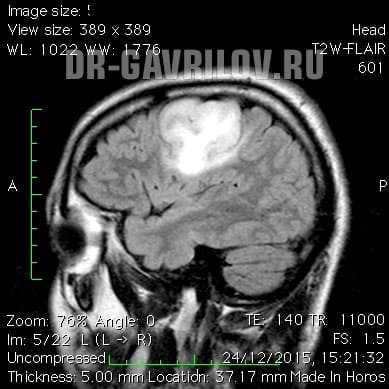

- Магнитно-резонансная томография - способна провести визуализацию опухоли в любом отделе головного мозга, выявить размер и пределы образования. В 98% случаях МРТ позволяет поставить точный диагноз. При необходимости процедура может проводиться с контрастом, что еще больше увеличивает информативность исследования.

- компьютерная (КТ) и магнитно-резонансная томография (МРТ) с контрастом - золотой стандарт при обследовании головного мозга, получаются высокоточные послойные изображения;